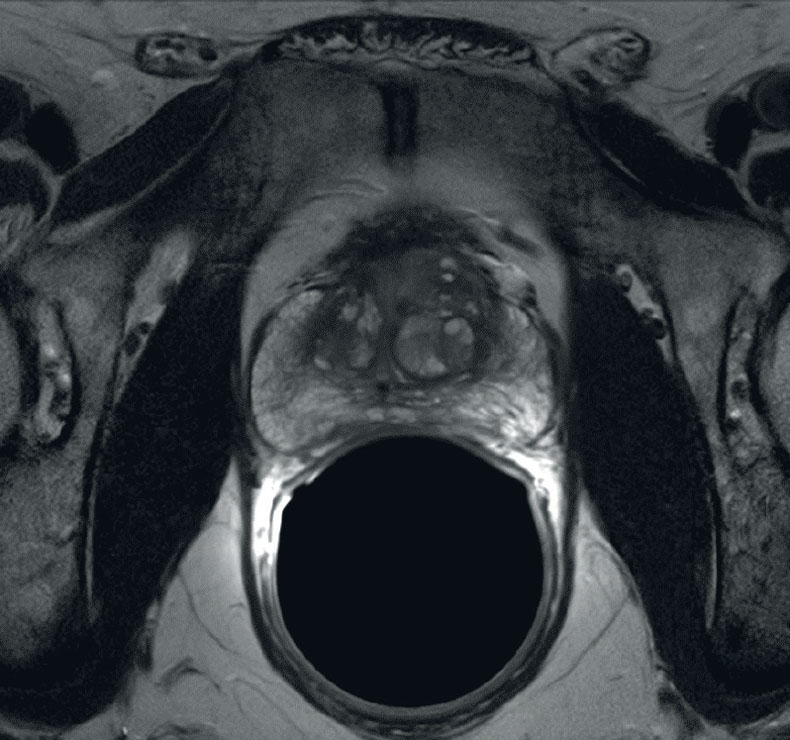

Prior TURP may also be a contraindication as this may allow seeds to overdose the urethra, which could lead to stricture or post-implant incontinence. With modern peripheral loading techniques, this may be less a contraindication than previously thought as complications have decreased. Linked seeds may be advantageous in this setting. Before any brachytherapy in a patient with a history of TURP can be considered, detailed imaging of the extent of TURP should be obtained and considered mandatory. T2 MRI and T1 post gadolinium will be helpful.

This is probably not the ideal prostate candidate for implant.